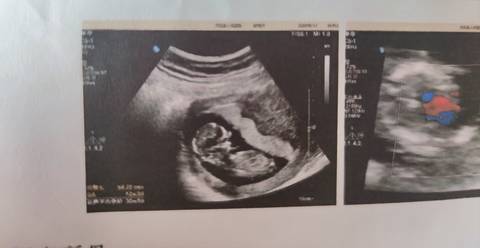

这个是男宝还是女宝呀?

亲爱的,通过这些判断不出来的哈,反正宝宝发育好就是最好的哈,祝你心想事成。加油

你好。根据数据图片看不出来的。是不科学依据的,孕期定期检查,只要宝宝健康就好。祝心想事成。

现在看不出来 宝宝健康就好